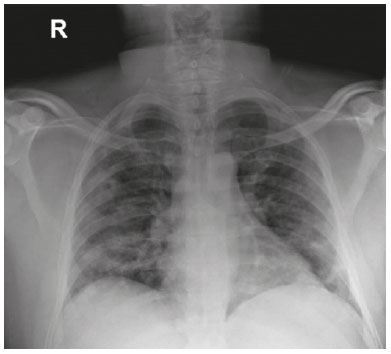

A 44-year-old generally healthy man who was referred for ophthalmologic consultation in a hospitalized institutional setting presented with a 5-day history of fever, double vision, and headache. The patient also reported fatigue, generalized muscle weakness, and loss of appetite for 1 wk. Several days before his admission, he had visited a healthcare practitioner and was sent home with antipyretic treatment. Owing to the absence of respiratory symptoms, COVID-19 was not suspected at that time. The patient had no known medical or ocular history, medications, or allergies. As his symptoms did not resolve, he was admitted to the hospital without any respiratory symptoms. Blood tests demonstrated mild lymphopenia (1.28 × 109/L), elevated C-reactive protein (92 mg/L), and D-dimer level (1.3 µg/mL) consistent with COVID-19. Lung auscultation and chest radiography indicated a bilateral pneumonia-like illness (Figure 1) that was asymptomatic. Computed tomography of the head showed no pathological findings (Figure 2). Reverse transcriptase-polymerase chain reaction (RT-PCR) was positive for SARS-CoV-2 in the patient’s first nasopharyngeal swab. Ophthalmologic examination, performed with complete personal protective equipment, revealed binocular diplopia and a limitation to abduction in the left eye. Orthophoria was noted in the right gaze. There was no additional cranial nerve involvement. Ophthalmologic examination, including pupillary response, anterior pole, and dilated fundus exam was otherwise unremarkable. Neurological examination showed normal results without any evidence of meningeal irritation. Lumbar puncture and magnetic resonance imaging were considered but not performed because symptoms resolved within 5 d of admission. Treatment included azithromycin and hydroxychloroquine for 5 d, as per the local infectious disease protocol. The patient was discharged to state-mandatory quarantine; 10 d thereafter, his condition had improved, and he tested negative for SARS-CoV-2.